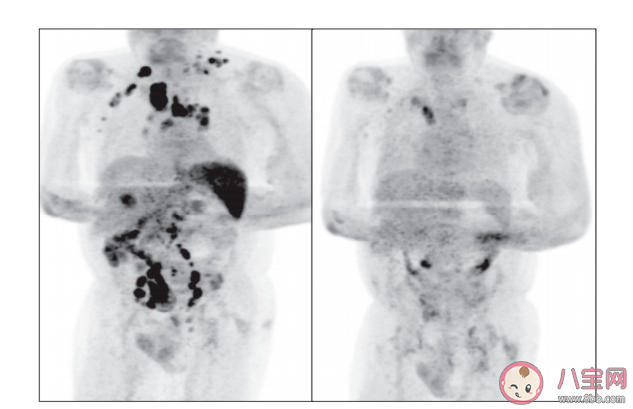

最近,《英國血液學(xué)雜志》發(fā)文稱,一61歲男性癌癥患者感染新冠肺炎后,體內(nèi)的腫瘤竟奇跡般消失了。這位患者的腫瘤消退,和患上新冠有關(guān)系嗎?

雖然目前仍未明確腫瘤消失的原因,不過專家們提出了這位患者癌癥自愈的一個(gè)假設(shè):

——新冠病毒的感染觸發(fā)了這名患者體內(nèi)的抗腫瘤免疫反應(yīng)。

新冠病毒入侵這位患者的身體時(shí),刺激了他的免疫系統(tǒng),免疫系統(tǒng)隨即釋放了大量促炎性細(xì)胞因子,促炎性細(xì)胞因子的釋放。

在無形之中激活了這位患者體內(nèi)兩種重要的免疫細(xì)胞:

1、自然殺傷細(xì)胞,這是一種能同時(shí)抗腫瘤,抗病毒的重要細(xì)胞。

2、抗原特異性 T 細(xì)胞,即免疫系統(tǒng)生成的專門對抗霍奇金淋巴瘤的免疫細(xì)胞。

兩種免疫系統(tǒng)同時(shí)作用產(chǎn)生了交叉反應(yīng)——兩種免疫細(xì)胞都能針對兩種不同的抗原起反應(yīng)。

也就是說這4個(gè)月里,這位病人的免疫系統(tǒng)在新冠病毒的刺激下,開啟了強(qiáng)大的“無雙模式”。

兩種被激活的免疫細(xì)胞交叉反應(yīng),同時(shí)對抗被新冠病毒感染的正常細(xì)胞和癌細(xì)胞。